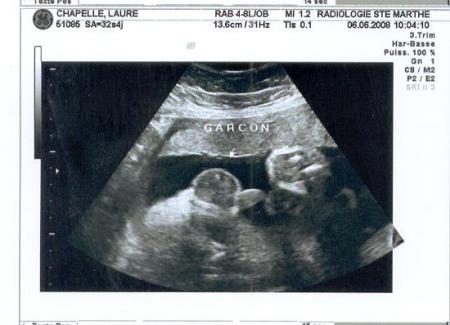

échographie du 3ème trimestre.

c'est la dernière ligne droite! nous sommes le 6 juin 2008. c'est la dernière fois que mes parents me voient sur le petit écran. 144 battements par minute, 2,210 kg. l'échographe n'a pas prit beaucoup de photos ce jour là à part ma colonne, mon coeur... et mon zizi!!! pour vous mesdames un petit aperçu. je m'excuse d'avance auprès de ceux qui se trouveront des complexes après ça!